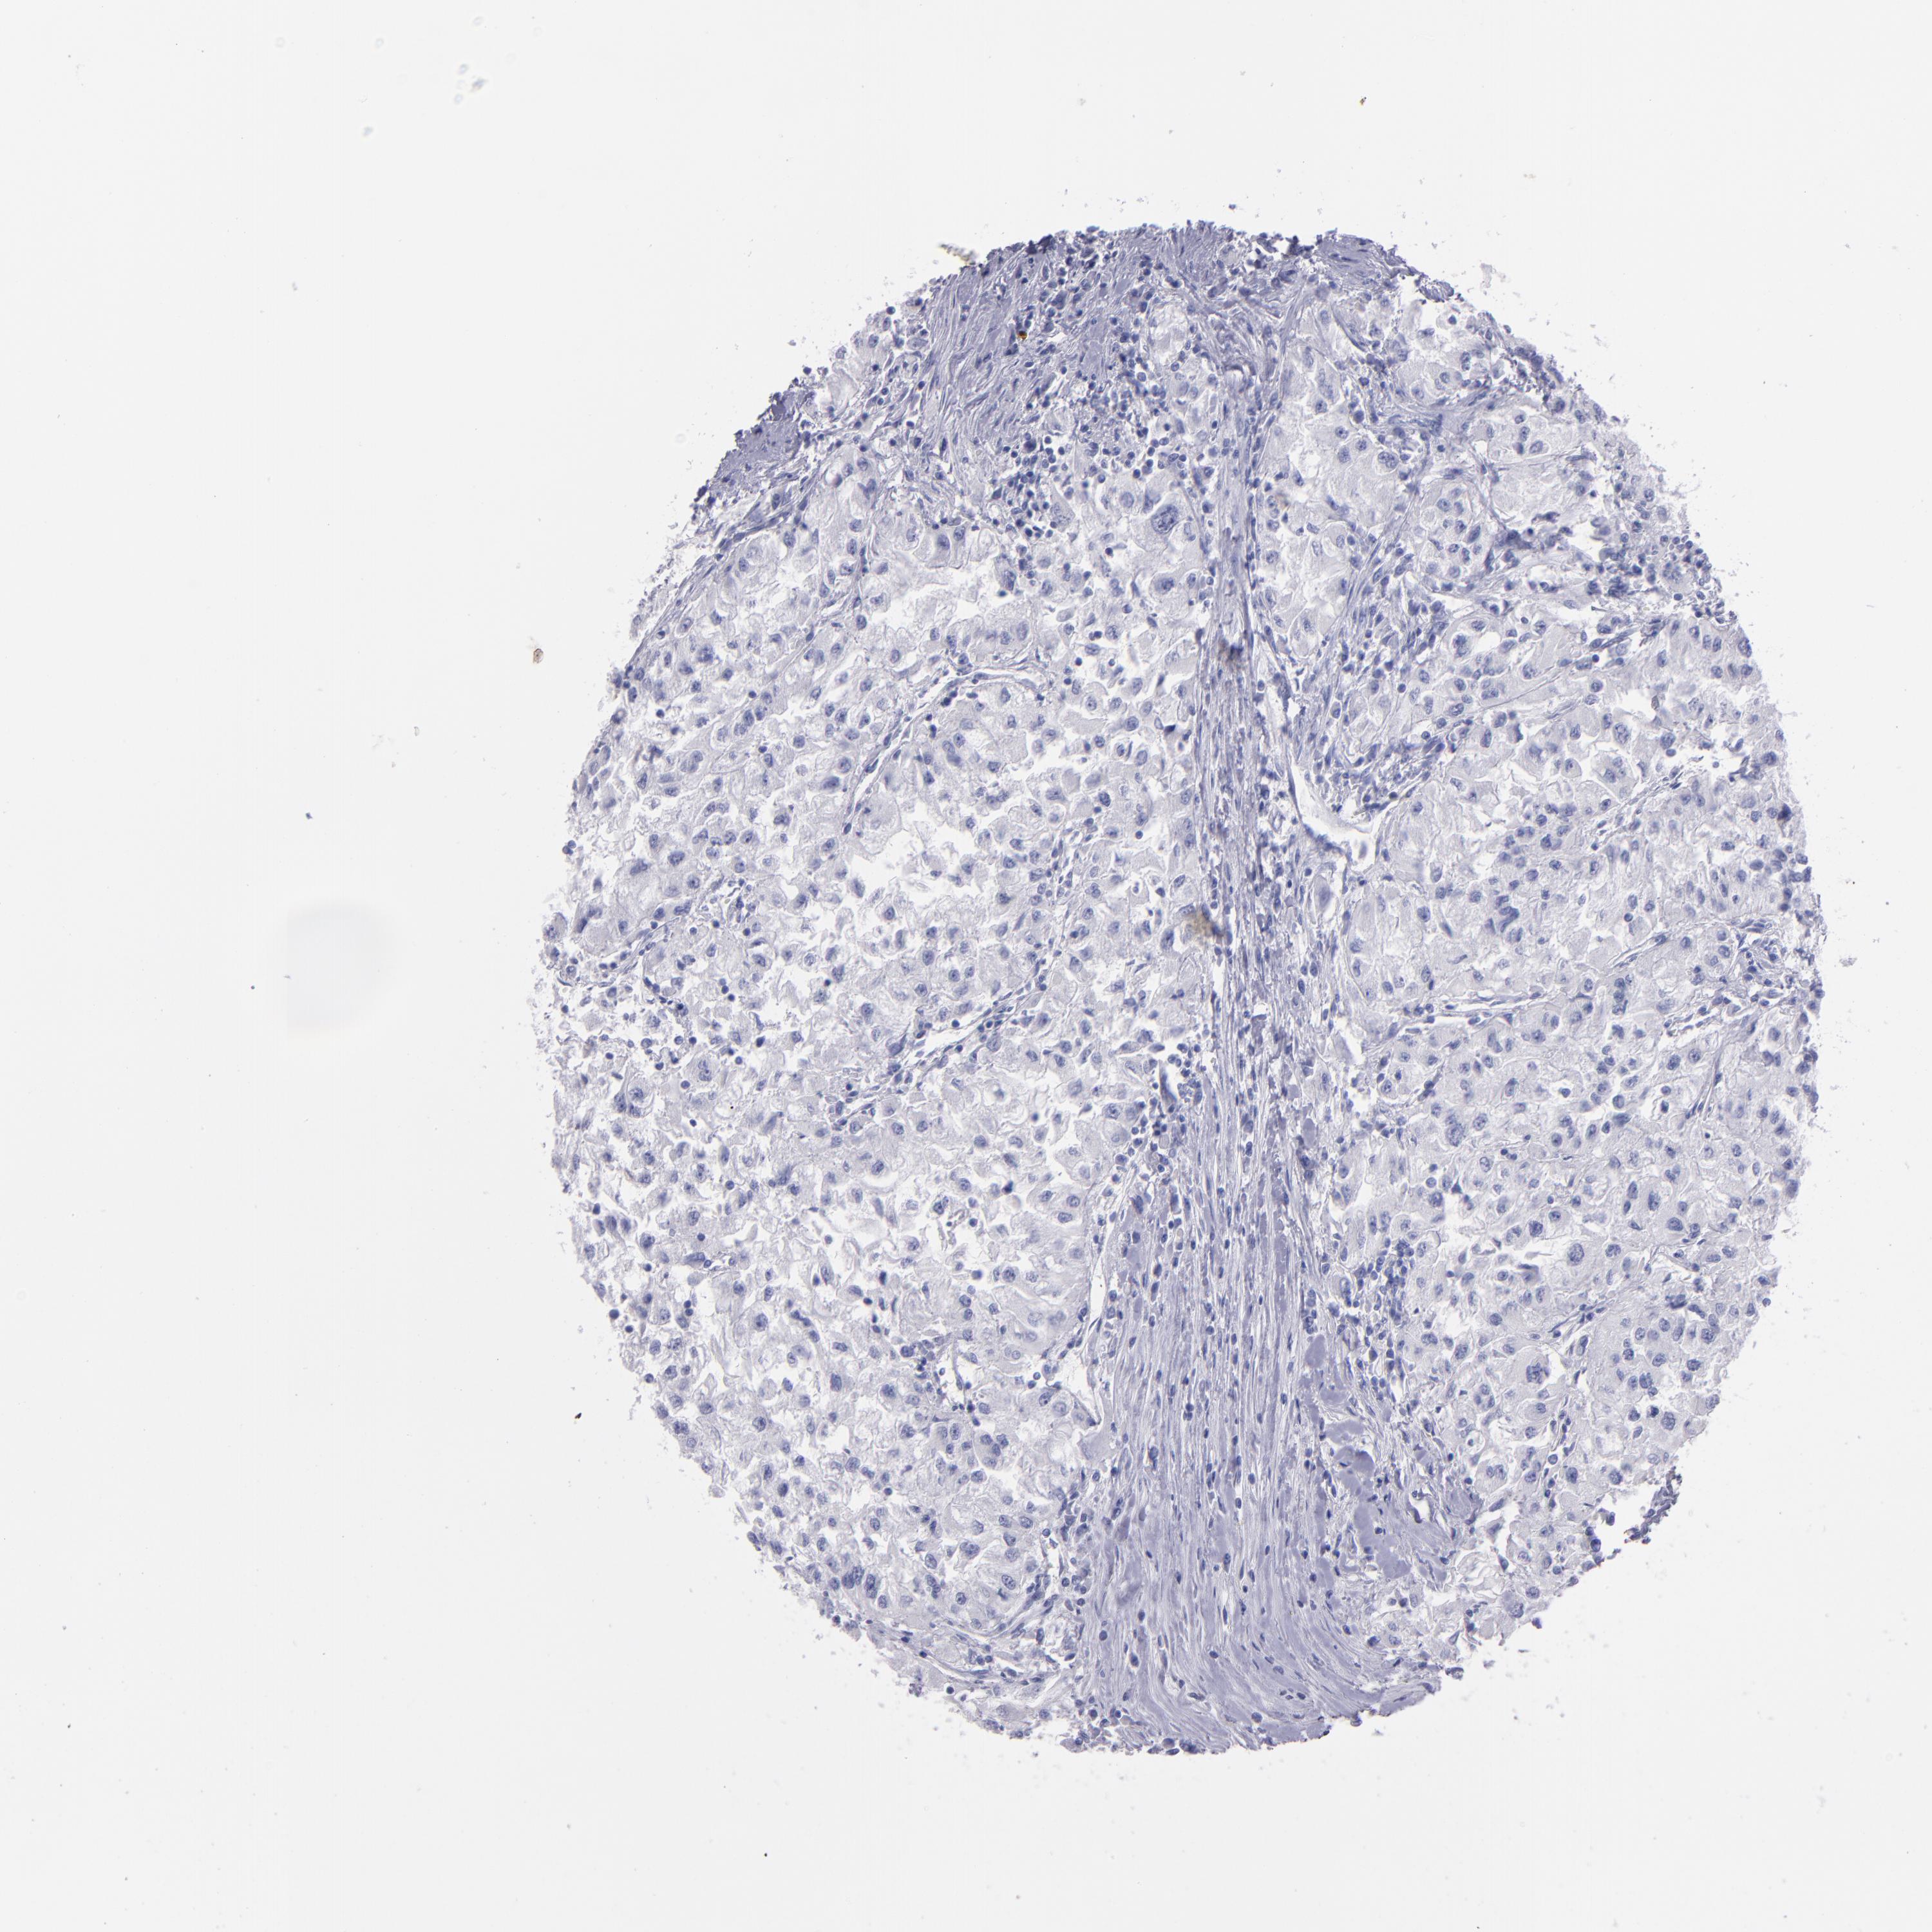

KIDNEY RENAL CLEAR CELL CARCINOMA (VALIDATION) - Interactive survival scatter ploti

The Survival Scatter plot shows the clinical status (i.e. dead or alive) for all individuals in the patient cohort, based on the same data that underlies the corresponding Kaplan-Meier plots. Patients that are alive at last time for follow-up are shown in blue and patients who have died during the study are shown in red.

The x-axis shows the expression levels (FPKM) of the investigated gene in the tumor tissue at the time of diagnosis. The y-axis shows the follow-up time after diagnosis (years). Both axes are complimented with kernel density curves demonstrating the data density over the axes. The top density plot shows the expression levels (FPKM) distribution among dead (red) and alive patients (blue). The right density plot shows the data density of the survived years of dead patients with high and low expression levels respectively, stratified using the cutoff indicated by the vertical dashed line through the Survival Scatter plot. This cutoff is automatically defined based on the FPKM cutoff that minimizes the p-score. The cutoff can be changed by dragging the vertical line or by entering a cutoff value in the square labeled "Current cut-off".

Under the Survival Scatter plot the p-score landscape (black curve; left axis) is shown together with dead median separation (red curve; right axis). Dead median separation is the difference in median mRNA expression between patients who have died with high and low expression, respectively. It is calculated as follows: median FPKM expression of dead patients with high expression - median FPKM expression of dead patients with low expression. This is intended to aid the user in visually exploring custom cutoffs and the associated p-scores and dead median separation.

Individual patient data is displayed and can be filtered by clicking on one or more of the category buttons on the top of the page. Categories describing expression level and patient information include: high, low, alive, dead, female, male and tumor stages. The scale of the x-axis can be toggled between linear and log-scale by clicking on the "x log" button. Mouse-over function shows TCGA ID, patient information and mRNA expression (FPKM) for each patient.

& Survival analysisi

Kaplan-Meier plots summarize results from analysis of correlation between mRNA expression level and patient survival. Patients were divided based on level of expression into one of the two groups "low" (under cut off) or "high" (over cut off). X-axis shows time for survival (years) and y-axis shows the probability of survival, where 1.0 corresponds to 100 percent.

TG is not prognostic in Kidney Renal Clear Cell Carcinoma (validation)

Best expression cut offi

Based on the FPKM value of each gene, patients were classified into two groups and association between prognosis (survival) and gene expression (FPKM) was examined. The best expression cut-off refers the FPKM value that yields maximal difference with regard to survival between the two groups at the lowest log-rank P-value. Best expression cut-off was selected based on survival analysis .

When clicking on this number, the vertical dashed line indicating cut-off, the interactive survival plot, and the Kaplan-Meier curve will be adjusted to show results based on the best expression cut-off.

: 1.36

P scorei

Log-rank P value for Kaplan-Meier plot showing results from analysis of correlation between mRNA expression level and patient survival.

N/A

TCGA RNA samplesi

RNA-seq data is reported as average FPKM (number Fragments Per Kilobase of exon per Million reads), generated by the The Cancer Genome Atlas (TCGA) .

Normal distribution across the dataset is visualized with box plots, shown as median and 25th and 75th percentiles. Points are displayed as outliers if they are above or below 1.5 times the interquartile range. FPKM values of the individual samples are presented next to the box plot.

Average pTPM 1.0

Number of samples 100